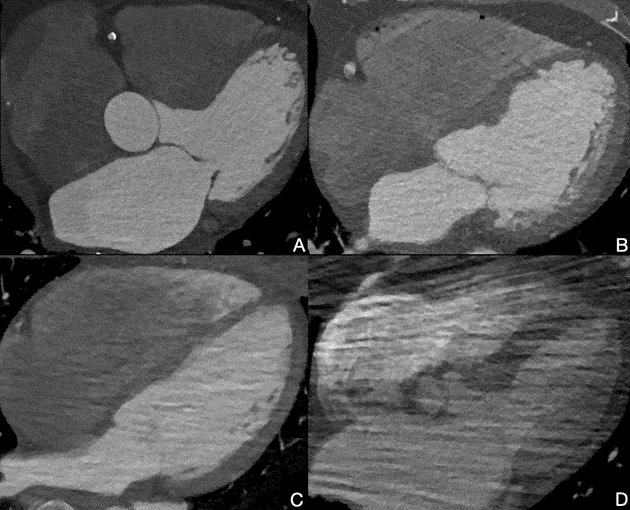

We hypothesized that non-ECG-gated high-pitch dual-source PCCT angiography from the diaphragm to the brain might provide added clinical value in detecting cardiac stroke sources during initial stroke imaging while maintaining optimal brain and neck image quality.

Consecutive patients with a clinical suspicion of acute stroke imaged with a PCCT system between October 4th, 2023 and April 13th, 2024 at a Swedish comprehensive stroke center were included. Diaphragm to brain coverage was obtained in an acquisition time of 1.3 seconds; on average, yielding a dose-length product of 360 mGy*cm for the study participants (2.34 mSv). Image quality was graded using a 4-point Likert scale. Images were assessed for cardiac stroke sources. Where available, reference standard echocardiography results were collected.

Image quality of the heart was excellent in 19 scans (9.8%) good in 97 (50.3%), moderate in 72 (37.3%), and poor in 5 scans (2.6%). Fourteen (7.3%) certain or probable interatrial septal defects were found in the study population. In the imaging-confirmed ischemic stroke subgroup, six certain or probable cardiac thrombi were found (4.8%). Additionally, a possible cardiac thrombus was found in 31 instances (24.6%). Three aortic valve vegetations were found (2.4%), all confirmed by echocardiography.

Non-ECG-gated high-pitch dual-source PCCT angiography typically provides images of high quality, at virtually no time expense while maintaining a reasonably low radiation exposure. Non-gated PCCT angiography is a promising technique to be used as a primary screening method for cardioembolic stroke.